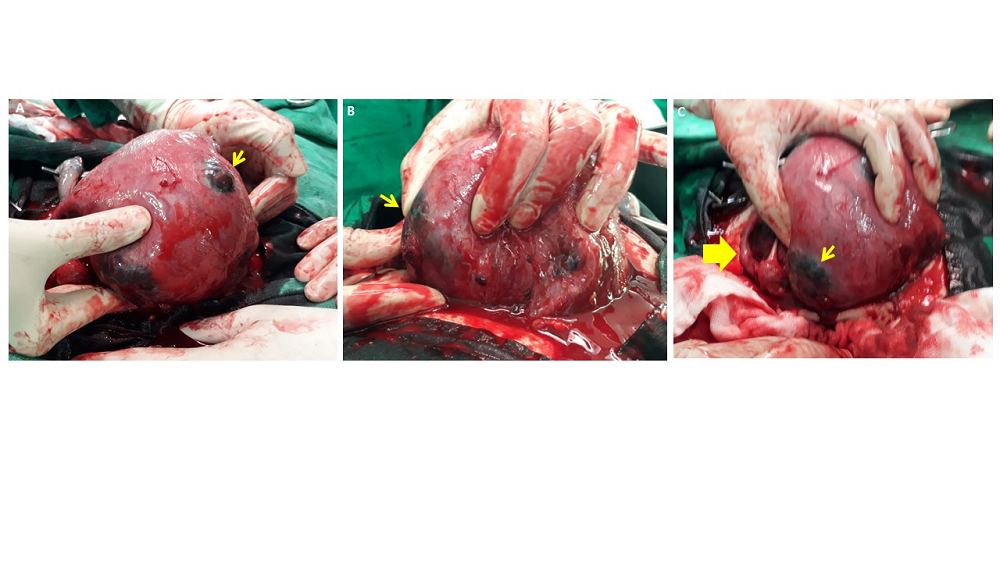

A 34-year-old woman, was 31 weeks and 4 days pregnant when she visited the emergency room with chief symptoms of abdominal pain and diarrhea for 3 days. She had undergone laparoscopic RFA for adenomyosis via M-1004 (RF Medical, Seoul, Korea) at a local hospital about three years prior. The patient succeeded in pregnancy after receiving in vitro fertilization and embryo transfer at a local infertility clinic and received regular checkups at another local hospital. She had abdominal pain three days before she visited and was taking a medication for enteritis because no special abnormal signs were found. She took the medicine; however, her symptoms gradually worsened. Her pain persisted, and she had a soft stool almost every hour. When she arrived at the emergency room, her vital signs were blood pressure 118/82 mmHg, body temperature 36.7 ℃, heart rate 101 beats/min, and respiratory rate 20 breaths/min. A blood test showed Hb 12.9 g/dL, WBC 7830/μL, platelet 173,000/μL, and CRP slightly increased to 1.0 mg/dL. There was no electrolyte imbalance, and otherwise no unusual test results. A fetal sonography showed the fetus presenting as vertex and the expected fetal weight was 1457 grams. The amniotic fluid index (AFI) was 9.7, an appropriate value, and the cervical length was 3.3 cm, with a T-shape. There was no leakage or pooling observed during the pelvic examination, and both the nitrazine and premature rupture of membrane (PROM) kit tests were negative. The fetal heartbeat was active, and uterine contractions appeared every 2 to 3 minutes during fetal cardiotoco-monitoring. After administration of the tocolytics, the patient symptoms improved; however, the patient complained of abrupt abdominal pain. The entire abdomen was tender; however, subplacental hematoma via ultrasound was not observed. Recurrent variable deceleration was observed without a uterine contraction in the cardiotocography (Figure 1); therefore, we performed an emergency cesarean section under the diagnosis of fetal distress. A large amount of blood and clots in the abdominal cavity was observed. A female baby was born, weighting 1.43 kg, with a 1 minute Apgar score of 4 and 5 minute Apgar score of 7. Placenta percreta with active bleeding was observed on the posterior wall of the uterus, and multiple lesions of placental percreta were also observed on the fundus, anterior, and posterior uterine wall (Figure 2). We experienced difficulty completely removing the placental invasion tissue, first considering that the severe adhesion was detected on the posterior uterine wall and the intestine. Therefore, we partially removed the placenta tissues and placed hemostatic sutures at the percreta sites, with two layers. The bleeding decreased, and the operation was completed while preserving the uterus. The patient was discharged from the hospital with a good overall condition on the seventh day after surgery. In the outpatient follow-up 6 months and 8 months after discharge, the posterior wall of the uterus had recovered, as shown via ultrasonography (Figure 3).

Figure 1.

Figure 1.— Cardiotocography performed on complaining severe abdominal pain. Recurrent variable decelerations (arrows) were observed without uterine contraction.

Figure 2.

Figure 2.— Placental percreta was observed on the fundus (A), anterior (B) and posterior wall(C) of Uterus, and uterine perforation(C, thick arrow) with active bleeding was observed on the posterior wall.